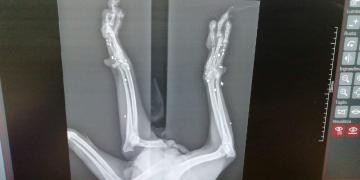

LIBERO Era solo un cucciolo….!!! Gli avevano sparato!! Fu trovato sofferente che zoppicava, nella periferia di Palermo, laddove abbandonano i cani non desiderati. FORSE LIBERO ERA RIUSCITO A SCAPPARE PRIMA CHE IL SUO CARNEFICE LO FINESSE Qualcuno si era divertito a sparare alle sue zampette.. Un cucciolo … come si puo’ fare questo ad un esserino innocente?

Adesso Libero si trova ancora in Sicilia in provincia di Palermo. Sono già passati 4 anni e per lui nessuno ha mai chiamato.. RIPROVIAMOCI.. Libero ha una zampetta impallinata che ha frantumato le ossa. Purtroppo non si puo’ intervenire chirurgicamente e cio’ gli impedisce di poggiarla in terra, ma questo non fa di lui un cane non autosufficiente. Libero è un cane dolcissimo di taglia media, bellissimo. Corre e gioca normalmente. Castrato e vaccinato e soprattutto negativo alla Leishmania.